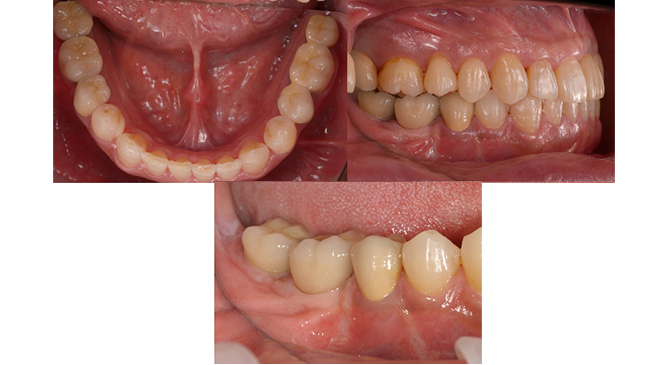

症例1

右下の奥歯の失った部位に対して、痩せた歯茎の再生治療とインプラント治療を行いました。

症例2

痩せてしまった下顎の骨を再生させる手術と歯茎を再生する手術を行い、3本のインプラント治療を行いました。